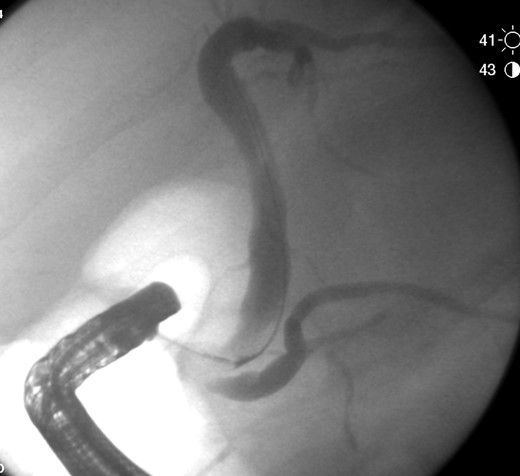

The patient was admitted for management of obstructive jaundice with possible cholecystitis. On hospital day 1 his bilirubin increased to 5.1, he was given Vitamin K and fresh frozen plasma to correct his coagulopathy and he was taken for endoscopic retrograde cholangiopancreatography (ERCP). During ERCP, the common bile duct (CBD) was cannulated and swept revealing a moderate amount of maroon clot (Fig. 2). No other debris or stones were noted to be within the CBD on final fluoroscopic image (Fig. 3).